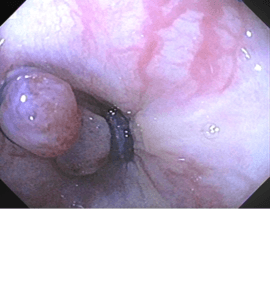

Polipectomía

La polipectomía es un procedimiento endoscópico que se utiliza para extraer pólipos en diversas partes del tracto gastrointestinal, como el esófago, estómago, duodeno o colon....